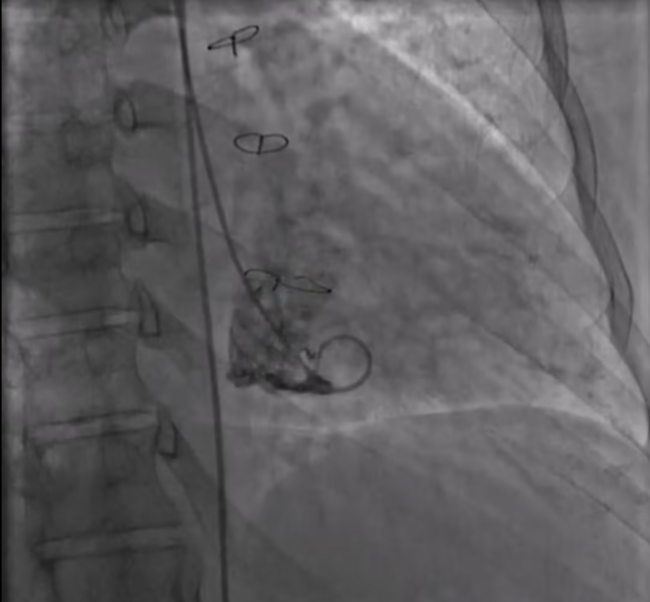

A 34-year-old female with Down’s syndrome (DS) and a history of ventricular septal defect repairs (first operation at 4.5 months and repeat repair at 5 years) was referred for worsening dyspnea on exertion and orthopnea. Echocardiography demonstrated severe primary mitral regurgitation (MR) secondary to anterior leaflet prolapse and suspicious anterior mitral leaflet cleft. She underwent a left heart catheterization that demonstrated severe MR (Video Series). Given 2 prior sternotomies, we felt that she would likely benefit from an edge-to-edge (ETE) transcatheter mitral valve repair (TMVr) with the MitraClip system (Abbott Vascular).

Intraoperative transesophageal echocardiography (TEE) demonstrated anterior mitral leaflet cleft and severe MR. MR jet was mostly from A2 and P2 at the vicinity of the anterior cleft (Figure 1A, Video Series). We grasped the A2 and P2 segments as close as possible to the cleft. A MitraClip XTW G4 device was placed on the A2 and P2 immediately adjacent to the cleft (Video Series), resulting in reduction of severe MR to mild MR (Figures 1B and 1C and Video Series). The mean gradient across the mitral valve was 5 mm Hg at a heart rate of 62 beats/min post clip deployment. The patient was extubated and had an uneventful recovery. She was discharged on postprocedure day 1. At 3-week follow-up exam, the patient had complete resolution of her dyspnea and orthopnea with significant improvement in exercise capacity.